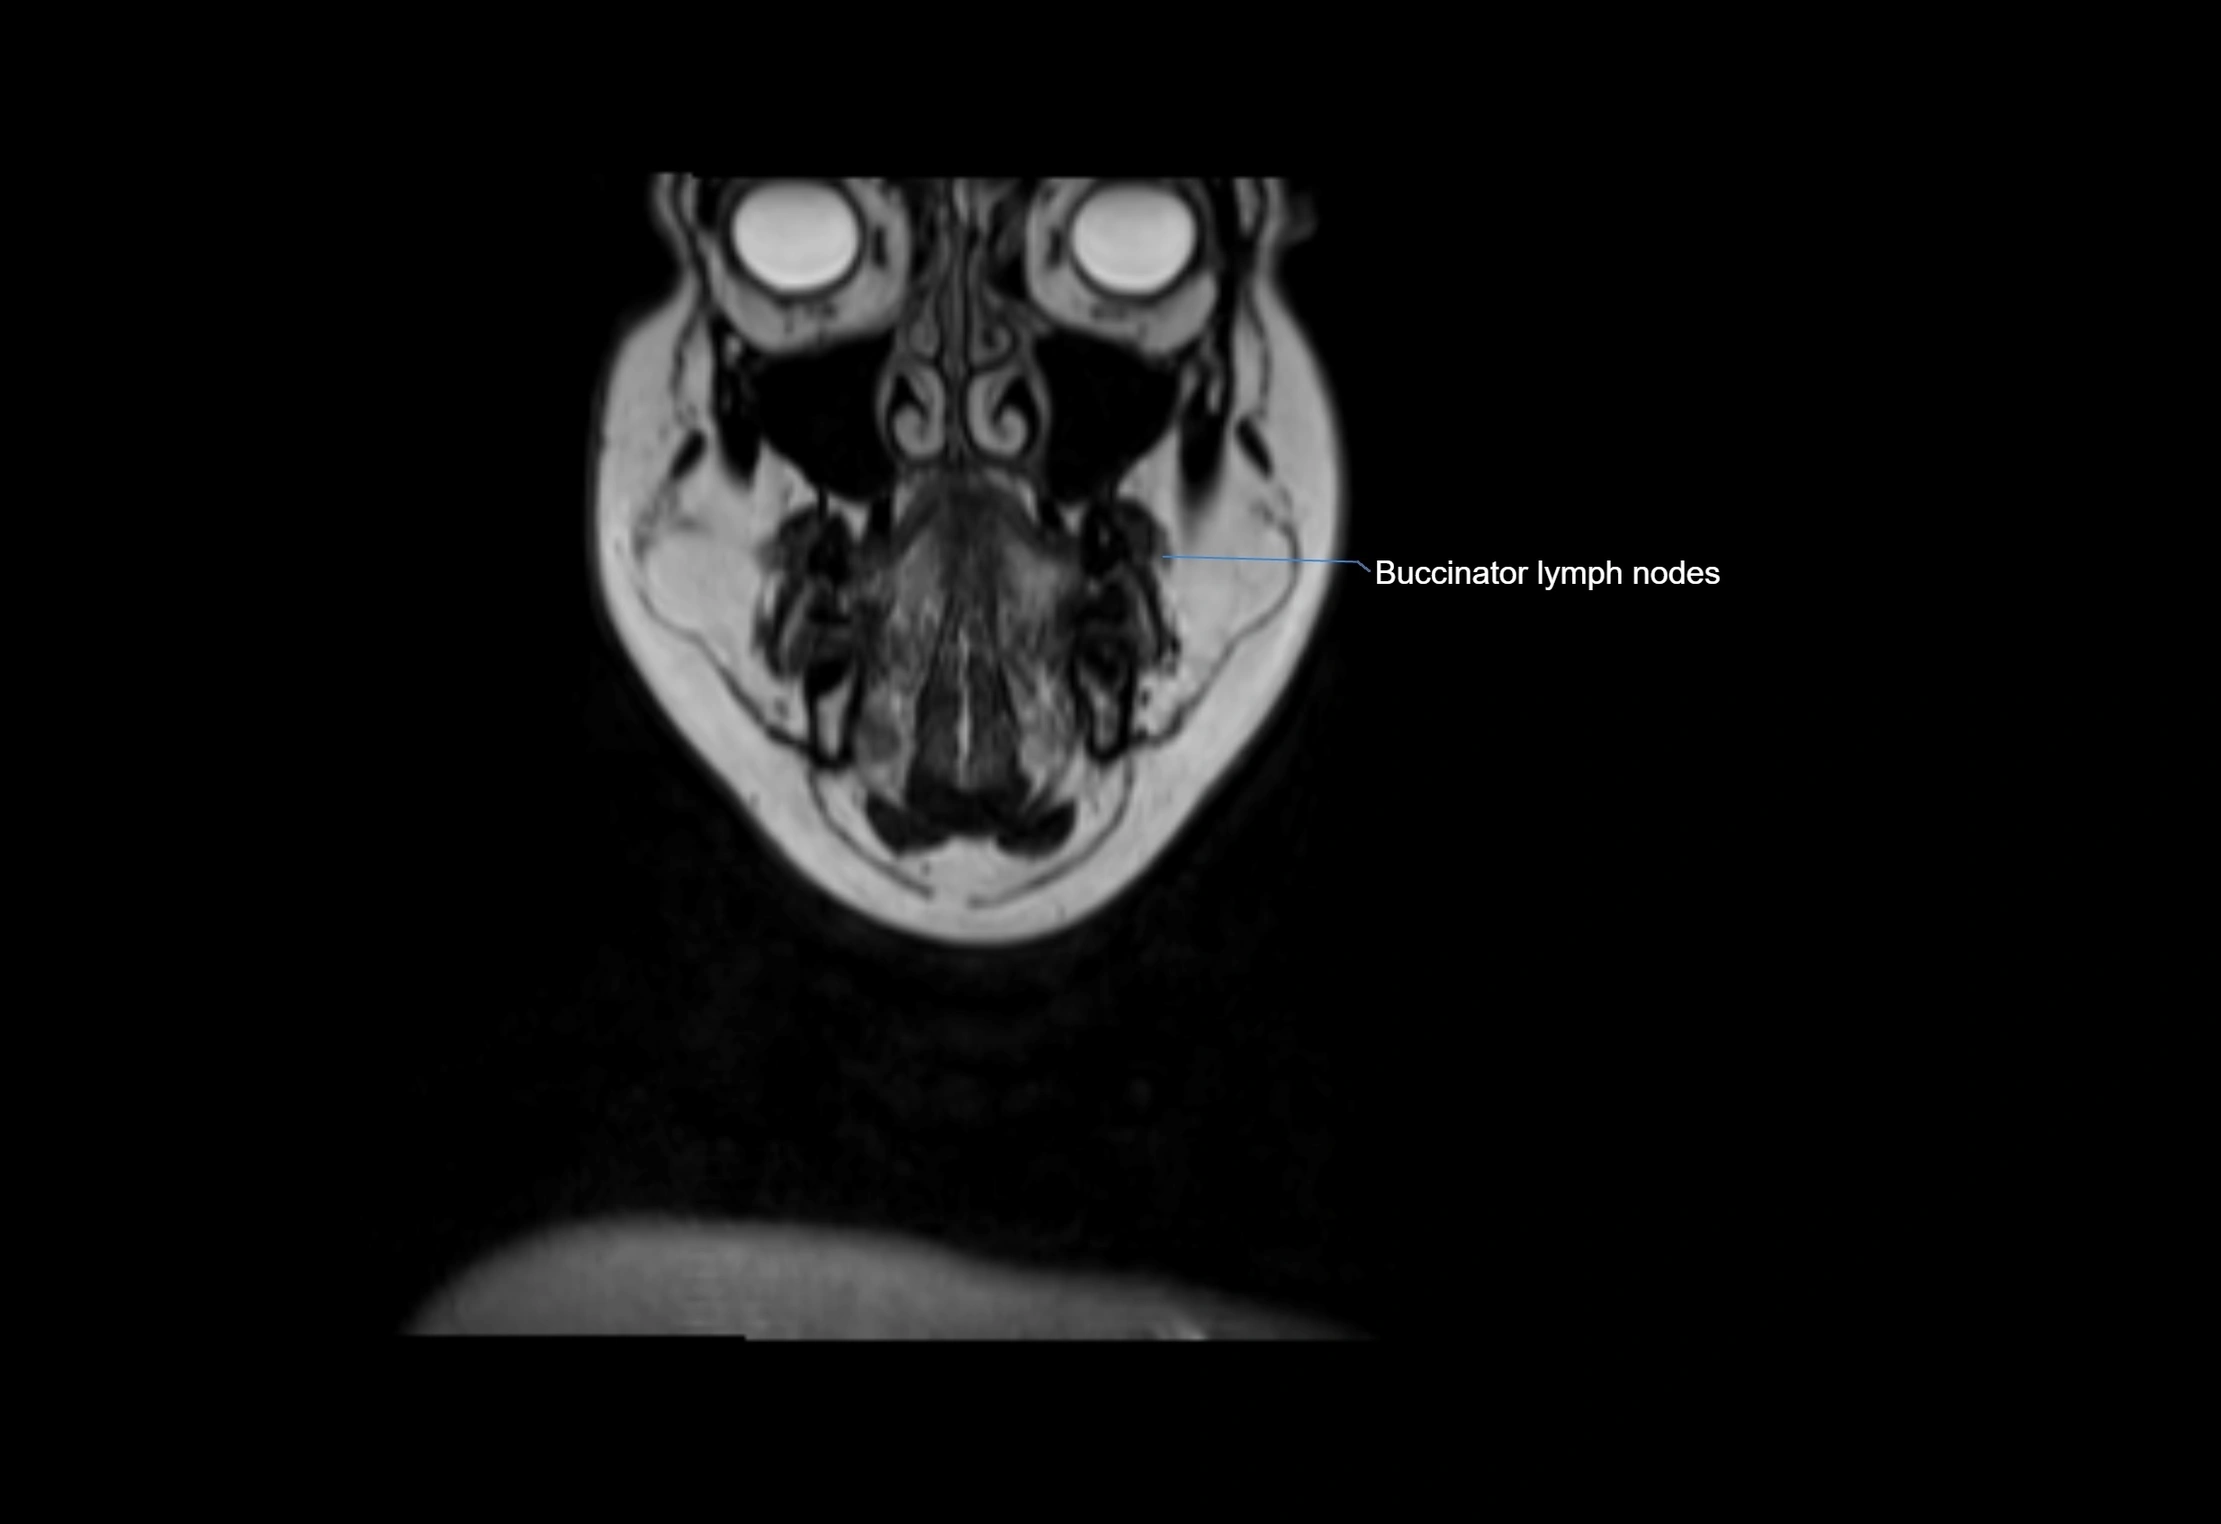

Location

• Found along primary lymph node chains, including preauricular, submandibular, parotid, and occipital regions

• Embedded in subcutaneous fat or superficial fascia, often lateral or posterior to primary nodes

Accessory lymph nodes are small, secondary lymph nodes located along the main facial and cervical lymphatic chains, often adjacent to primary lymph nodes, such as preauricular, submandibular, or occipital nodes. They are typically less than 5 mm in diameter, embedded within subcutaneous fat or connective tissue, and may be variable in number and location. These nodes provide additional filtration and immune surveillance for lymph collected from the face, scalp, and neck regions. Accessory lymph nodes are usually non-palpable in healthy individuals but may enlarge in response to infection, inflammation, or metastasis, making them clinically significant.

MRI Appearance

T2-weighted images:

• Nodes show intermediate signal, with surrounding fat bright

• Useful for detecting edema, inflammation, or infiltration